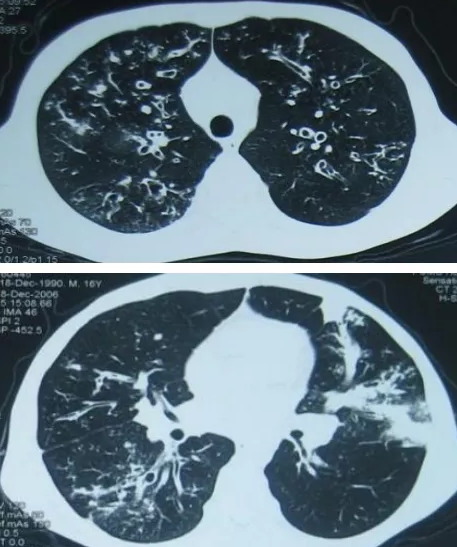

支气管扩张(以下简称支气管扩张)是指支气管持续扩张,并伴有支气管壁损坏。它是胸外科最常见的呼吸道慢性化脓性疾病。病理上,支气管壁受损,扩张变形持久不可逆,伴有周围肺组织的慢性炎症。近几十年来,药物治疗效果显著,致病因素明显减少,发病率大幅下降, 并发症也明显下降。慢性咳嗽、咳脓痰、反复咯血是支气管扩张的临床表现。这种疾病多见于儿童和青少年,但可见于儿童和青少年。...